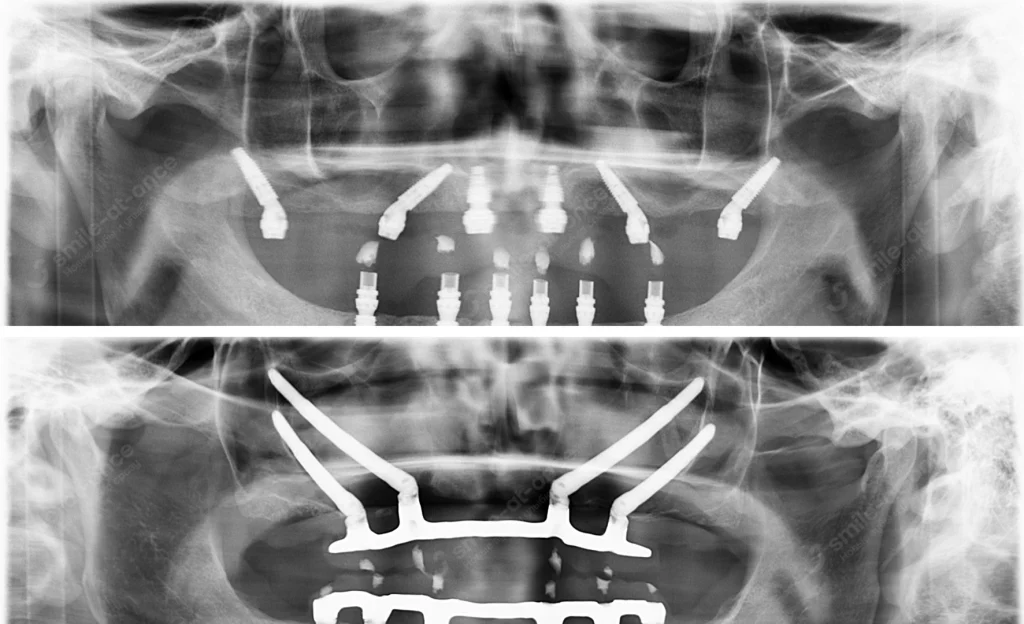

- Планируются протоколы All-on-4/All-on-6, транссинусальная/трансназальная имплантация, V-II-V, скуловые импланты.

Классика современной полной реабилитации. Две фронтальные опоры + две (или четыре) наклонные дистальные опоры под углом 30–45°. За счёт угла и длины импланта мы «переносим» опору на более плотные участки, минуя синус или зону атрофии. Часто — «зубы за 1–3 дня».

Скуловые импланты (Zygoma)

При выраженной атрофии верхней челюсти — мой главный инструмент, когда нужна имплантация без костной пластики. Длинные импланты фиксируются в кость скулы — это как поставить мост на скальные сваи. Пациент получает несъёмный адаптационный протез за 2–3 дня, через 8–12 месяцев — постоянную работу.